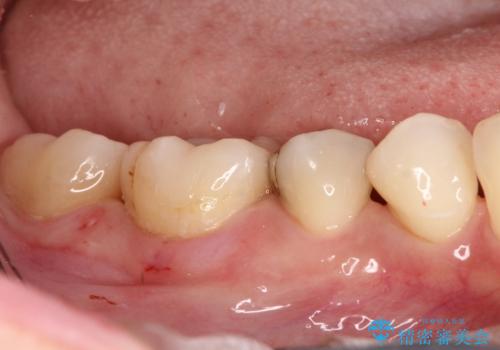

保険診療のCRインレーをセラミックインレーでやり直し

- 定期検診にて他院で治療された保険適用CRインレー部分(大臼歯2本)にむし歯を認めたため、セラミックインレーにて修復を行いました。

e-max プレスインレーにて修復治療を行っているため適合性及び審美性の高い治療を行うことができます